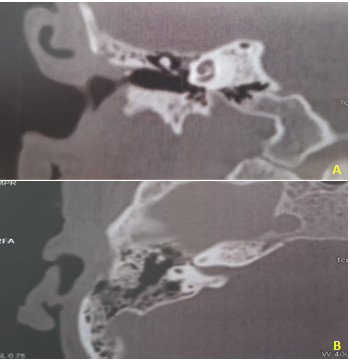

A CT of the temporal bone was performed and showed only the partial veiling of the middle ear and mastoid cells by material with soft tissue density (Figure 3). Then, the secretion was collected for glucose measurement (since the measurement of β2 transferrin was not available), which suggested CSF. A new CT of the ears was performed, and this time with identification of a small bone defect in tympanic tegmen.

Figure 3 Preoperative Computed Tomography of temoral bone.

A. Coronal section. B. Axial section. There is a tympanic tegmen bone defect and partial veiling of the middle ear and mastoid cells.